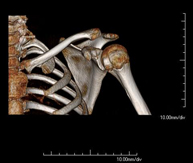

- Shoulder CT

Radiological examination based on an X-ray system and detectors that rotate around the patient, reconstructing the images by computer (multidetector computed tomography - MDCT) to study the bones, muscles and joints of the shoulder.